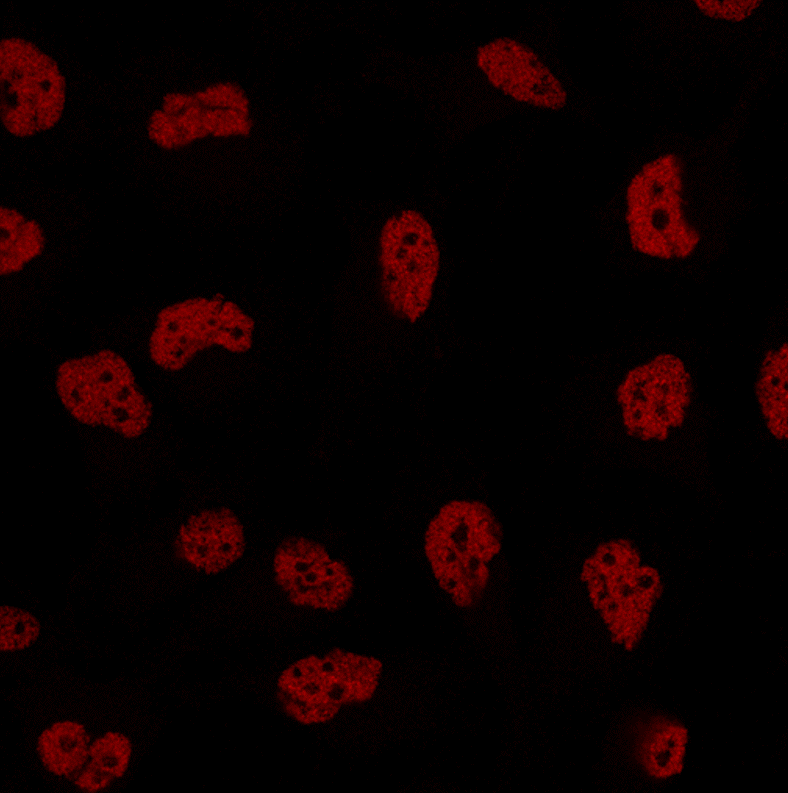

Triple negative breast cancer cells dividing in a laboratory cell culture. Credit: Laura Pascual/Centro de Regulación Genómica